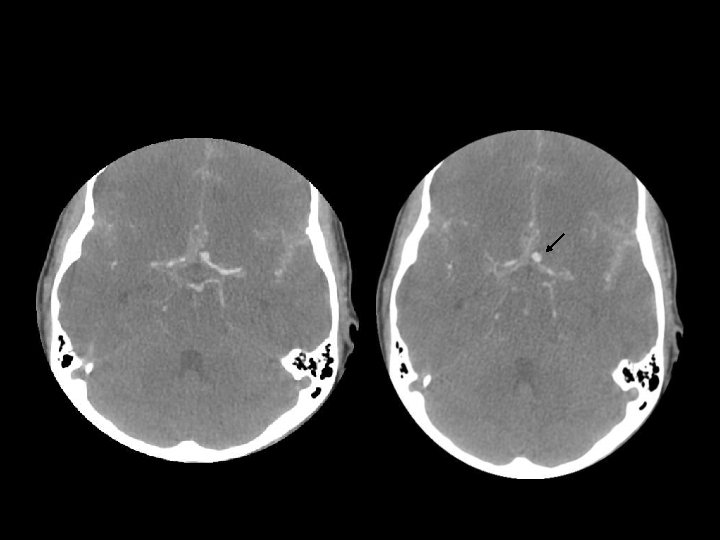

DIFFUSE AXONAL INJURY n Jarang terdeteksi pada CT ( 20% dari lesi DAI berupa perdarahan) n MRI: T 1, T 2 GRE, SWI

DAI n Akibat akselerasi / deselerasi terhadap white matter + hipoksia n Patients have severe LOC at impact n Grade 1: kerusakan axonal pada WM saja -67% n Grade 2: WM + corpus callosum (posterior > anterior) – 21% n Grade 3: WM + CC + brainstem

DAI n Beberapa jam : n Perdarahan dan robekan jaringan n Axonal swellings n Axonal bulbs n Beberapa hari/minggu : clusters of microglia and macrophages, astrocytosis n Beberapa bulan/tahun : Wallerian degeneration